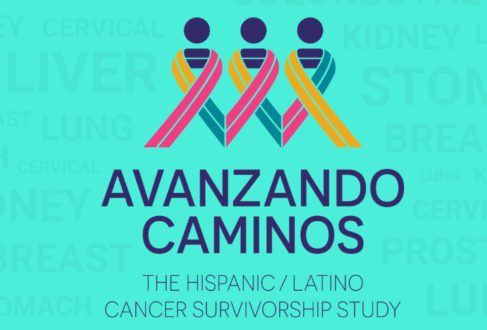

Share Your Cancer Story with the Avanzando Caminos Team

Just like fingerprints are tailored to the individual they belong to, no two cancer survivor stories are the same. Yet, every single one is important.

Researchers seek Hispanic cancer survivors for study on post-treatment life

Avanzando Caminos aims to understand the impact of various types of cancers on the Hispanic community. [...]

Science & Medicine: The Avanzando Caminos Hispanic cancer survivor study

Nearly 70 percent of San Antonio’s population is Hispanic, said Amelie Ramirez, who holds a doctorate in public health and is chair of Population Health Sciences at UT Health San Antonio, and that population is being hit particularly hard by cancer. [...]

Coastal Living TV features Avanzando Caminos Study at UT Health San Antonio

Did you know cancer is among the leading causes of death for Hispanics, along with heart disease and diabetes. […]